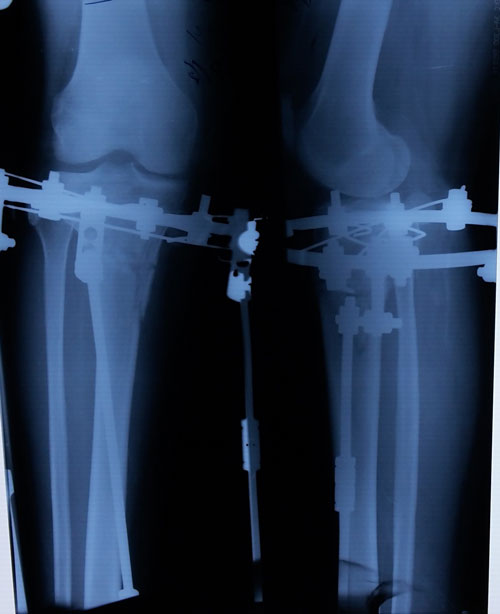

Re: Терачина♥♥♥

Дата операции 03.12.2015г.

Дата снятия аппаратов 09.03.2016г.

Срок лечения 95 дней.

Поздравляю

Результат супер!!!!